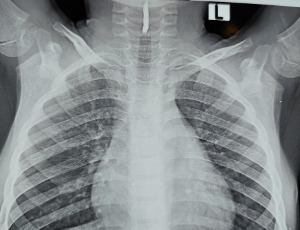

Tuberculous pericarditis with cardiac tamponade in a patient receiving adalimumab

Background: Tuberculous pericarditis is a rare manifestation of tuberculosis in developed countries and poses a significant diagnostic challenge due to its nonspecific clinical presentation. Immunocompromised individuals, particularly those receiving tumor necrosis factor-alpha (TNF-α) inhibitors, are at substantially increased risk of developing tuberculosis. Therefore, screening for tuberculosis infection and active disease is essential prior to initiating biological therapy.